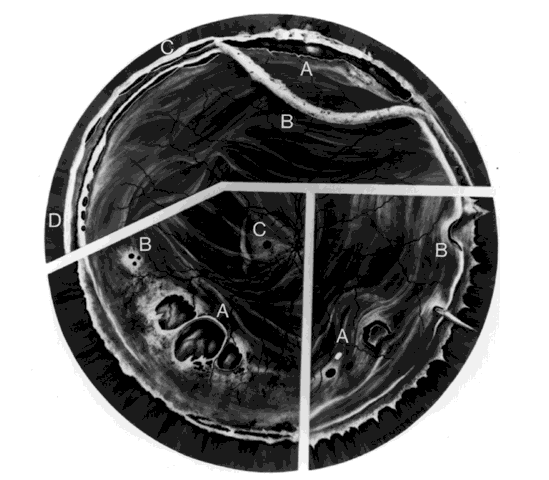

Retinal breaks are created at the time of nonpenetrating blunt injuries3 in 10% to 20% of eyes.3–6 Retinal dialyses are most frequent2–6 and are most often found in the lower temporal (Fig. 2) and upper nasal periphery (Fig. 3).2 Large irregular breaks at the point of impact of blunt trauma are less common but are equally characteristic of nonpenetrating injuries (see Fig. 3).2,7,8 Horseshoe and opercular tears of the equatorial retina (see Fig. 3) are associated with the more characteristic breaks in 25% of eyes.2 Small round holes in atrophic retina at the point of traumatic impact and macular holes (see Fig. 3) are infrequently observed after ocular contusion.2,8

Fig. 3. Top. Traumatic vitreous base traction. A. Upper nasal dialysis. B. Avulsed vitreous base. C. Dialysis at anterior vitreous base border. D. Tenting-up of retina and pars plana epithelium. Bottom left. Retinal breaks without vitreoretinal attachments. A. Large irregular breaks at the point of impact of blunt trauma. B. Small round holes in atrophic retina. C. Macular hole. Bottom right. Horseshoe and opercular tears. A. Of the equatorial retina. B. At the posterior vitreous base border.